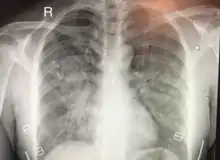

Chest x-ray of HAPE showing characteristic patchy alveolar infiltrates with right middle lobe predominance.

Hypoxic pulmonary vasoconstriction (HPV) occurs diffusely, leading to arterial vasoconstriction in all areas of the lung. This is evidenced by the appearance of "diffuse," "fluffy," and "patchy" infiltrates described on imaging studies of climbers with known HAPE.[8]

On physical exam, increased breathing rates, increased heart rates, and a low-grade fever 38.5o C (101.3o F) are common.[8][3] Listening to the lungs may reveal crackles in one or both lungs, often starting in the right middle lobe.[8][3] Imaging studies such as X-ray and CT imaging of the chest may reveal thoracic infiltrates that can be seen as opaque patches.[13][8][3] One distinct feature of HAPE is that pulse oximetry saturation levels (SpO2) are often decreased from what would be expected for the altitude. People typically do not appear as ill as SpO2 and chest X-ray films would suggest.[8][3] Giving extra oxygen rapidly improves symptoms and SpO2 values; in the setting of infiltrative changes on chest X-ray, this is nearly pathognomonic for HAPE.[3]

The severity of HAPE is graded. The grades of mild, moderate, or severe HAPE are assigned based upon symptoms, clinical signs, and chest x-ray results for individuals.[7] The symptoms that are taken in to account while evaluation the severity of HAPE are difficulty breathing while exerting or while at rest, the presence of a cough and the quality of that cough, and the level of fatigue of the patient. On physical exam of a suspected HAPE patient the exam findings used to grade the severity are the heart rate, respiratory rate, signs of cyanosis, and severity of lung sounds.[7] Both symptoms and signs on physical exam can be used to evaluate a patient in the field. Chest X-rays are also used to evaluate the severity of HAPE when they are available.